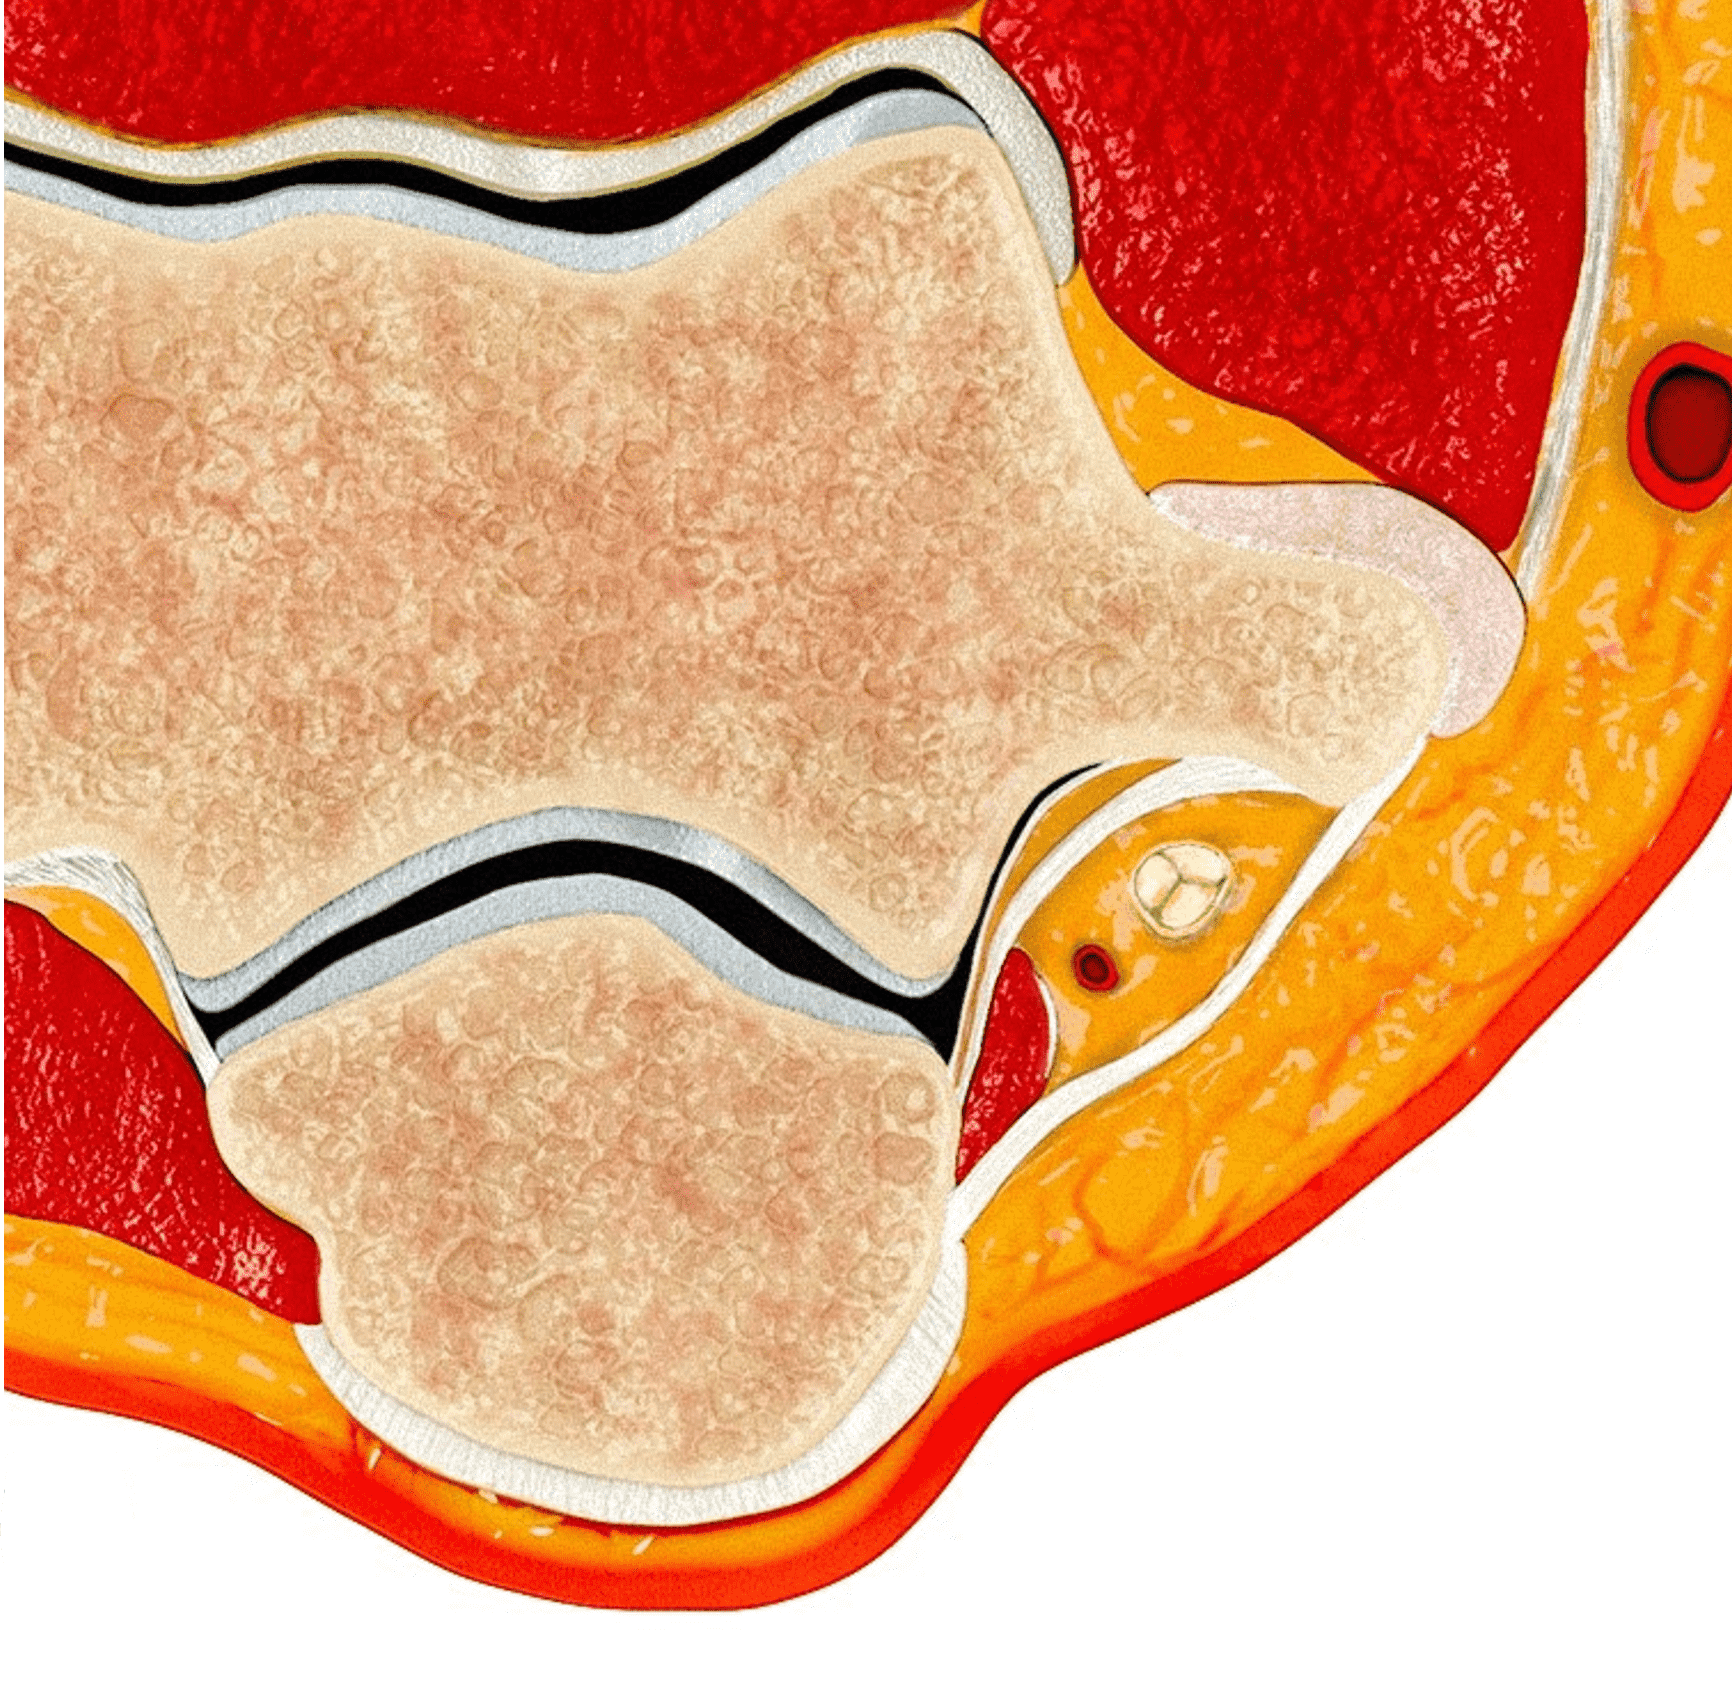

The cubital tunnel is a fibro-osseous space along the dorsoulnar aspect of the elbow joint, roughly triangular in cross-section (Figure 3). The medial humeral epicondyle and olecranon process of the proximal ulna form the anterior and lateral walls of the tunnel, respectively. A myofascial retinaculum joining these two bones (Osborne’s ligament) comprises the roof of the tunnel, and more distally the cubital tunnel retinaculum blends with a tendonous band that connects the two heads of the flexor carpi ulnaris muscle.4 Anatomic variations of the cubital tunnel retinaculum are common, and can contribute to the development of ulnar nerve pathology.5 The distal-most fibers of the medial head of the triceps muscle may extend into the proximal cranial portion of the cubital tunnel along the medial aspect of the olecranon. The posterior band of the ulnar collateral ligament (UCL) and the elbow joint capsule lie along the floor of the tunnel.6 The ulnar nerve and the posterior ulnar recurrent artery are located within the tunnel, surrounded by loose connective tissue and fat. The nerve can have one to several macroscopic fascicles, which may be visible on high-resolution ultrasound or fluid-weighted MRI studies (Figure 4).7,8

Figure 3: Normal cross-sectional anatomy of the cubital tunnel. (3A) Drawing showing a cross section of the elbow (3A) and an enlargement of the cubital tunnel (3B). The cubital tunnel retinaculum forms the roof of the tunnel. The posterior band of the ulnar collateral ligament and the posteromedial elbow joint capsule lie along the tunnel floor, and the distal muscle belly of the medial head of the triceps is present adjacent to the olecranon. The ulnar nerve and a branch of the ulnar artery are the main structures within the tunnel. Axial T1-weighted image (3C) demonstrates the corresponding anatomy: O = olecranon process of the proximal ulna, ME = medial humeral epicondyle, t = medial head triceps muscle, blue arrow = elbow joint capsule, red arrow = posterior band of the ulnar collateral ligament, arrowheads = cubital tunnel retinaculum, asterisk = ulnar nerve. The posterior ulnar recurrent artery is the round structure along the posterolateral aspect of the ulnar nerve.